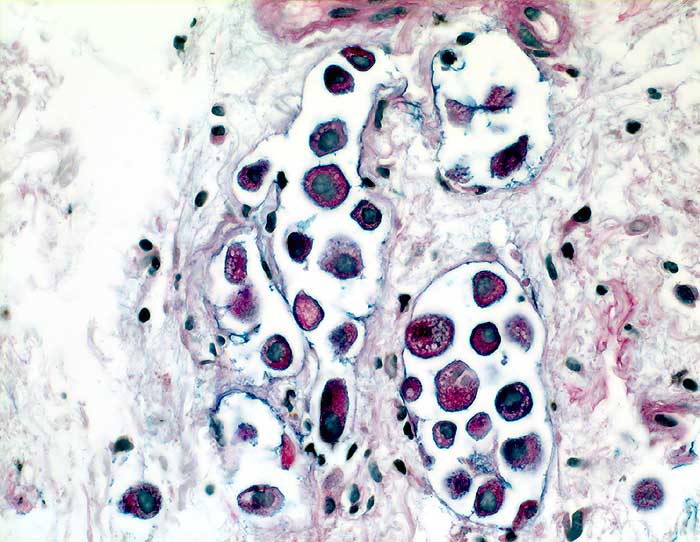

Adenokarzinom der Lunge: Lymphangiosis carcinomatosa

Einzeln im Lumen von Lymphgefässen liegende Tumorzellen mit reichlich intrazellulärem Schleim.

Autopsiebefund: peripheres Adenokarzinom der Lunge

Verdacht auf malignen Pleuraerguss

Histologie

400